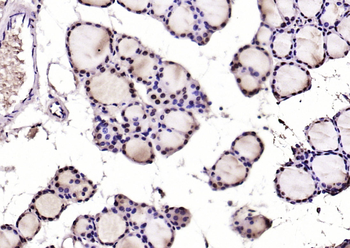

100 μl, 50 μl, 25 μl - Rad51 Recombinant Rabbit Monoclonal Antibody [orb608069]Featured

IF, IHC-Fr, IHC-P, WB

Human, Mouse, Rat

Mouse, Rat

Rabbit

Recombinant

Unconjugated

50 μl, 100 μl - KLF4 Recombinant Rabbit Monoclonal Antibody [orb608075]Featured